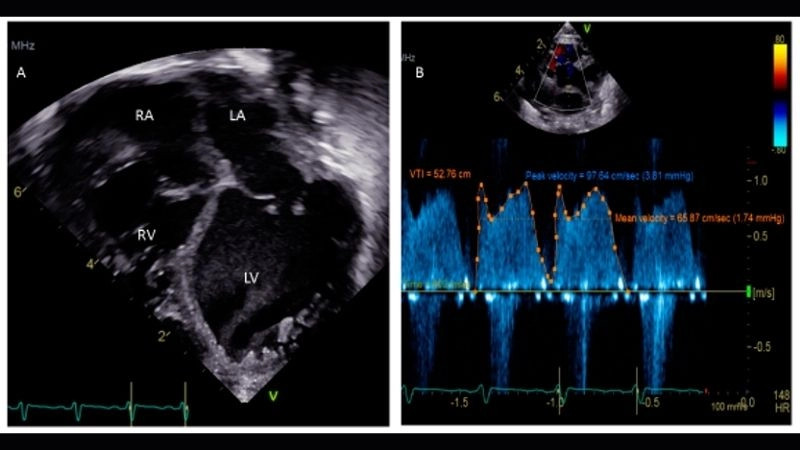

Images visual examples of patent foramen ovale (PFO)

Patent foramen ovale is a heart condition where a small flap-like opening between the left and right atria fails to close after birth. Visual examples often show its location within the atrial septum and how blood flow may bypass normal circulation.

PFO diagnosis tests to detect hidden heart condition